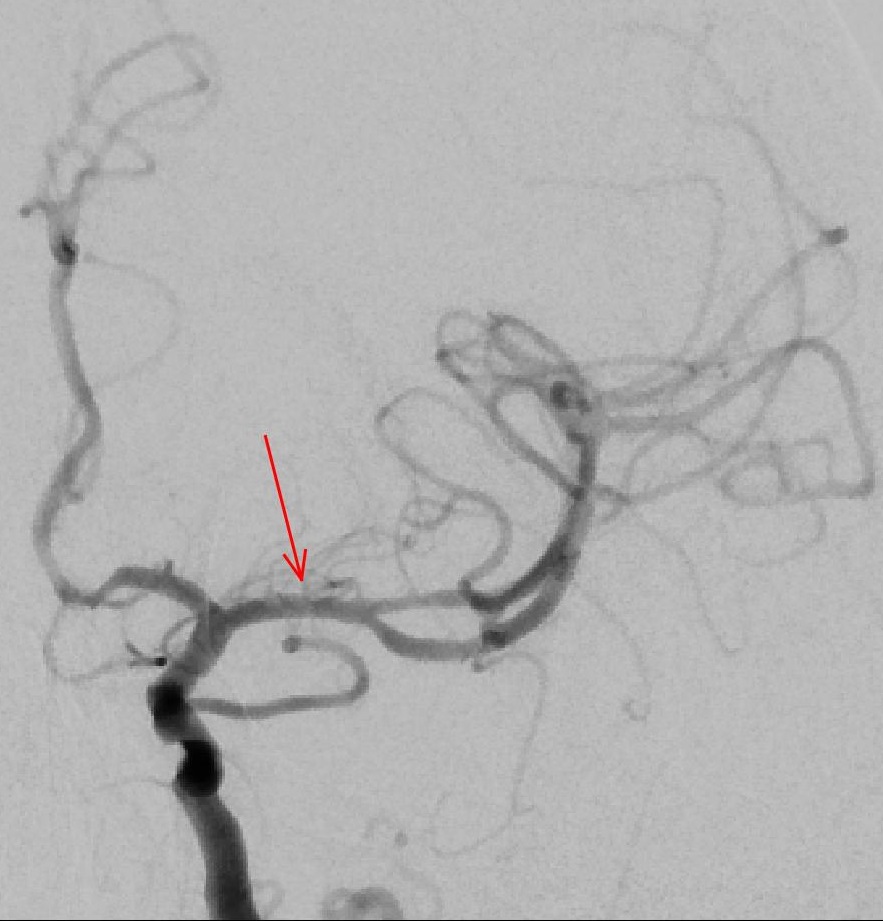

Neben der Behandlung der extrakraniellen hirnzuführenden Gefäße (Arteria carotis, Arteria vertebralis, Arteria subclavia und Truncus brachiocephalicus) werden in ausgewählten Fällen auch intrakranielle Stenosierungen (der rote Pfeil in der linken Aufnahme zeigt eine Stenose in der mittleren Hirnarterie, die rechte Aufnahme zeigt das Gefäß nach Behandlung) in unserer Klinik behandelt.